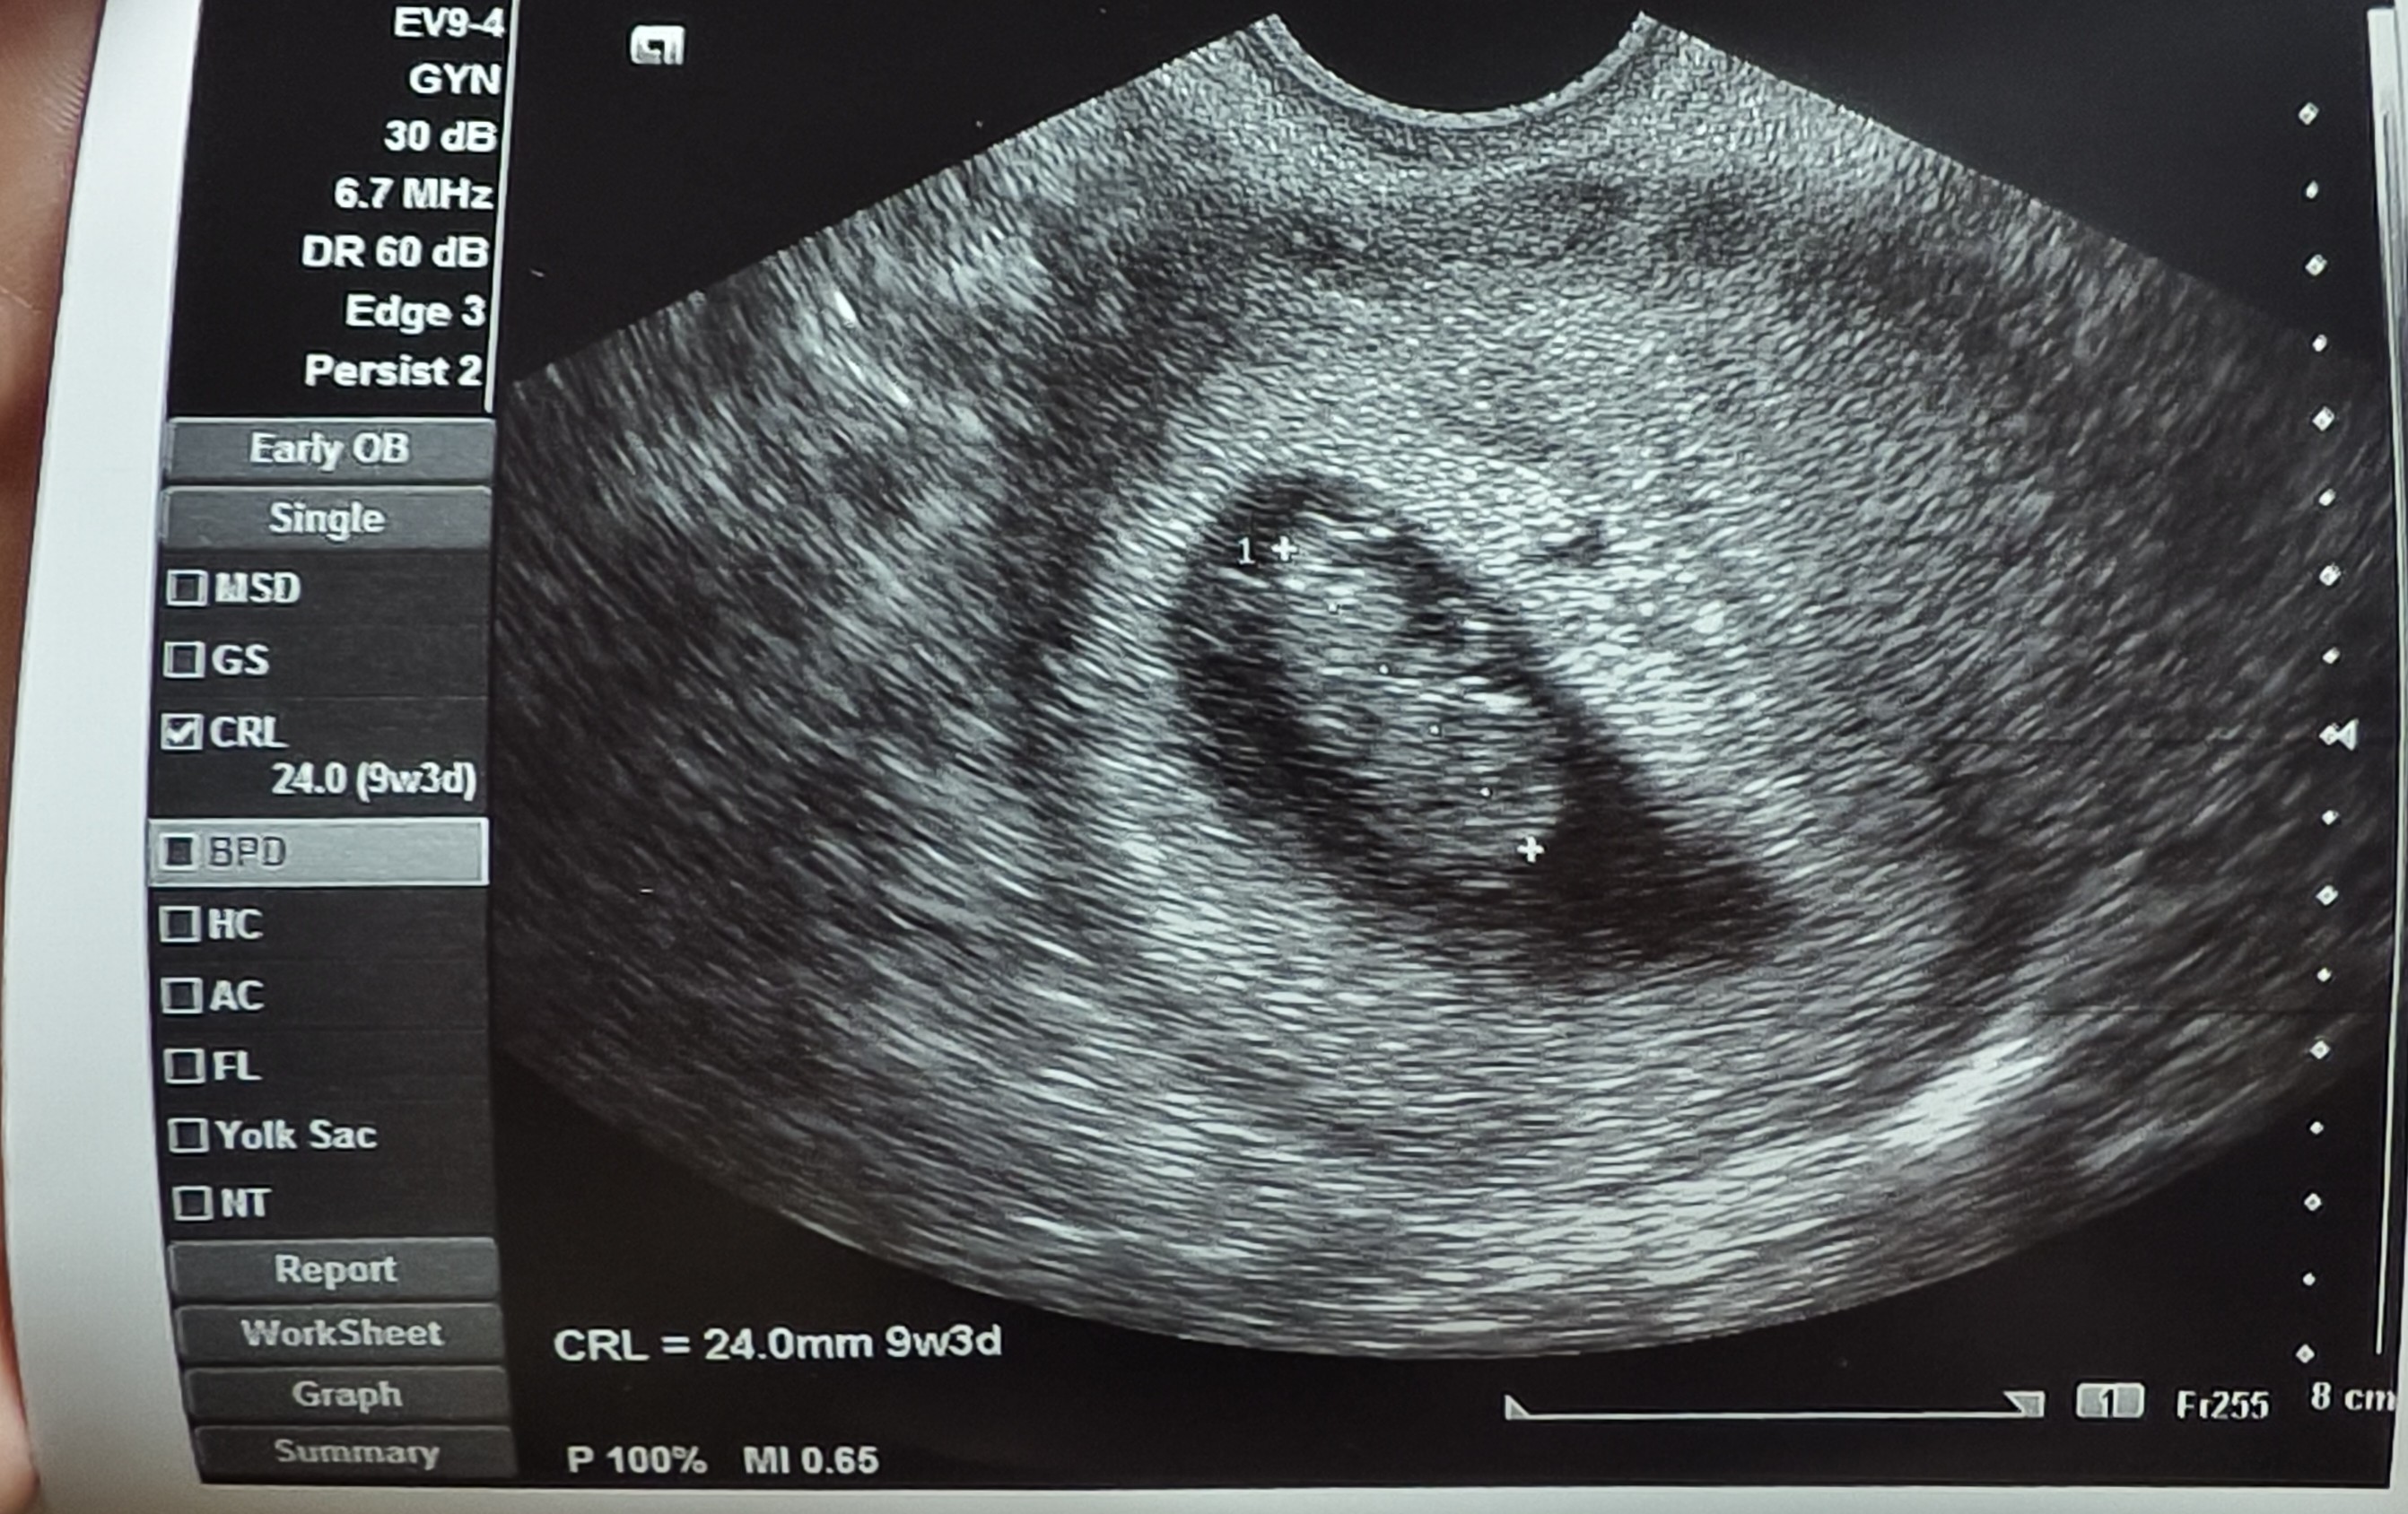

Ja byłam 9go u gina na nfz na kontroli i Wszystko pięknie, badania na razie też spoko, jedynie już na eutyrox 25mg jestem. Jutro mam wizytę u mojego gina wieczorem to zobaczę jak tam

. A prenatalne umówione mam na 3go listopada.